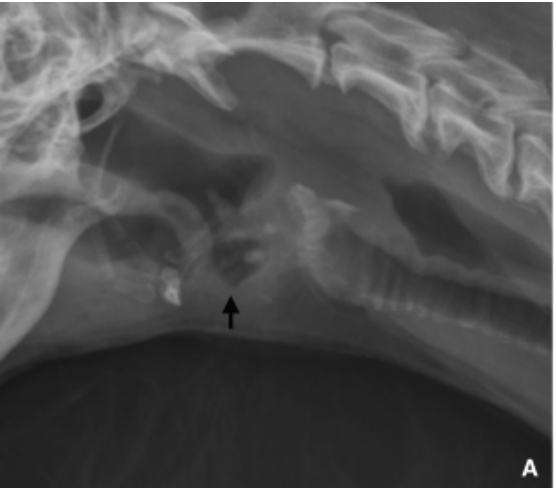

Regarding aortic lesions in dogs with spirocercosis:

Kirberger, R.M., Stander, N., Cassel, N., et al. (2013) Computed tomographic and radiographic characteristics of aortic lesions in 42 dogs with spirocercosis. Veterinary Radiology and Ultrasound 54, 212–222